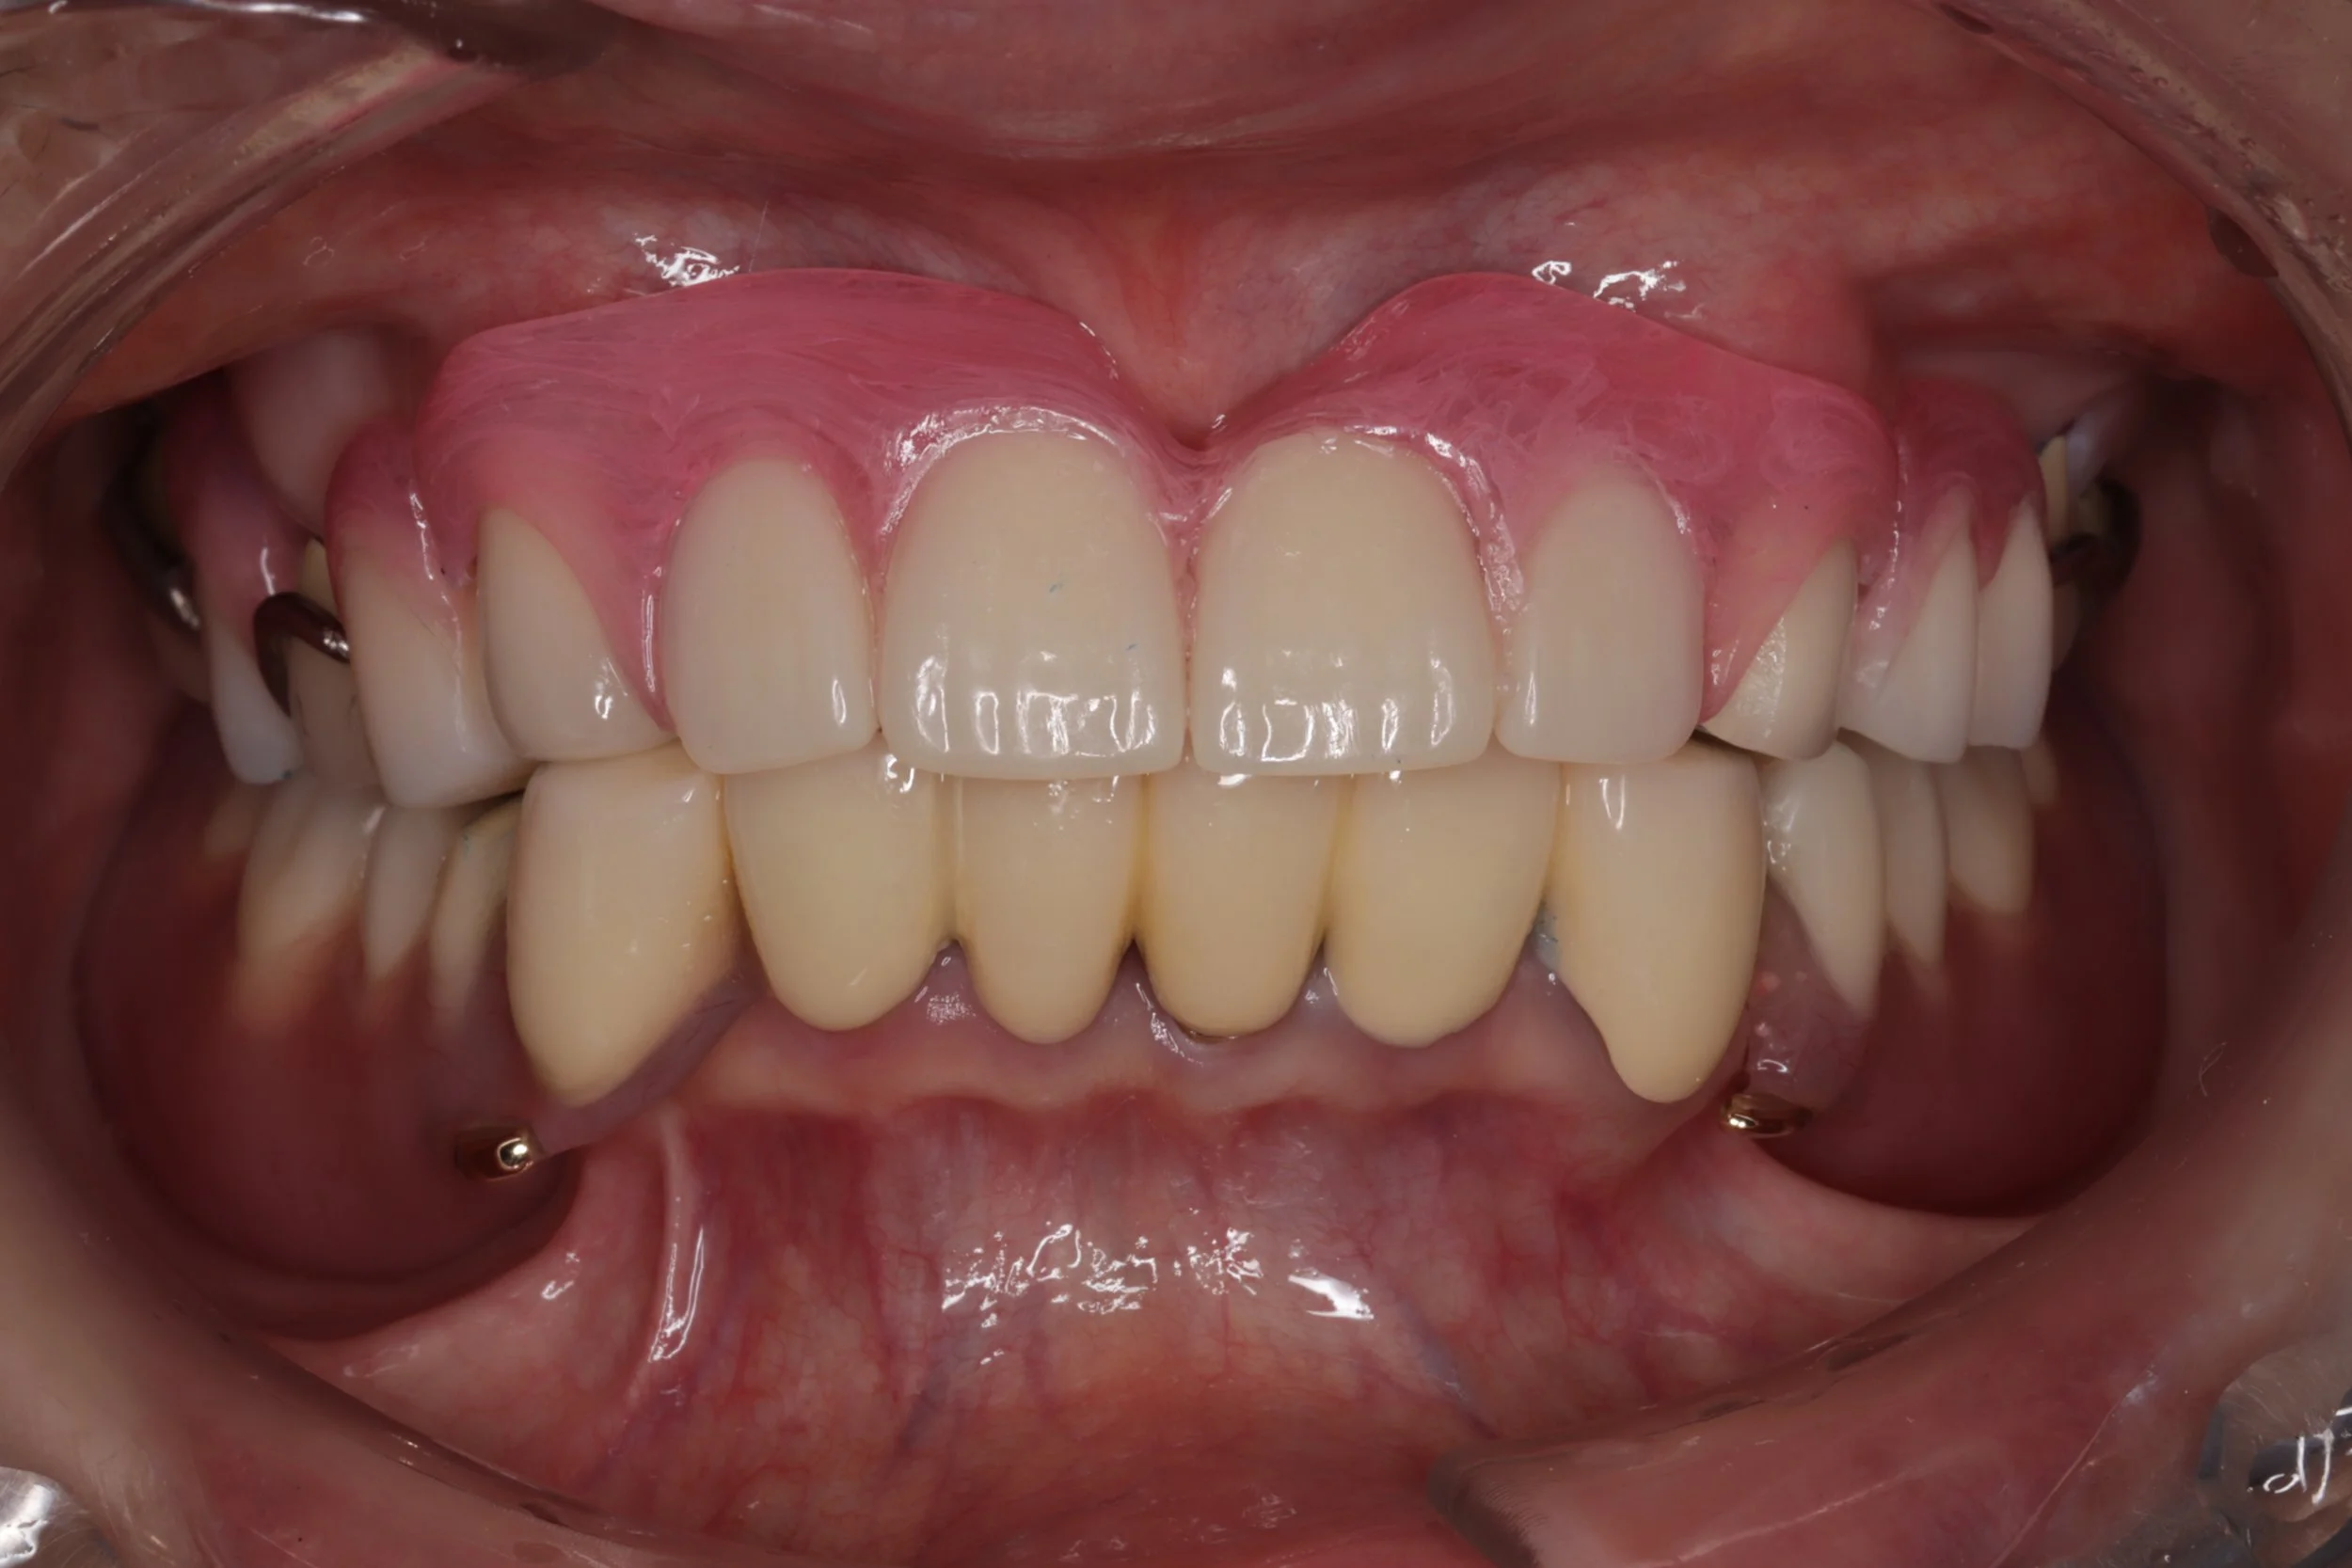

今回はできるだけ薄く作りたいという希望もあったことから、金属床を用い製作、前歯の抜歯とともに同日に新しい入れ歯を装着。

デジタルデンチャー

奥の歯には、金属で入れ歯を止めるバネを製作し、前歯の見える部分には、透明なレジンクラスプを使用しました。